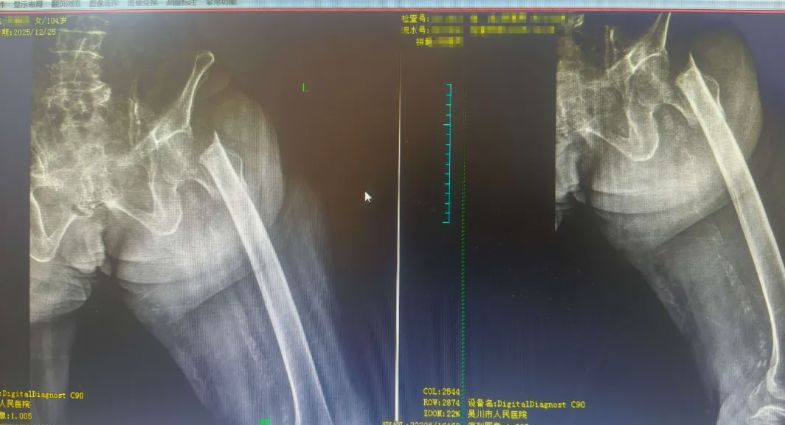

104岁的患者陈阿姨因跌倒导致左股骨颈基底部骨折、左股骨上段粉碎性骨折,同时伴有脑梗死、冠心病、心功能不全等十余种内科疾病。面对如此高龄且病情复杂的患者,手术风险极大,保守治疗又可能因长期卧床引发致命并发症。

经过骨外科二区李玉春主任医师和黄国聪副主任医师的全面评估,与家属充分沟通后,决定为患者实施微创经皮复位PFNA术。团队组织疑难危重病例讨论,制定个性化治疗方案,克服了高龄患者麻醉难度大、手术风险高等重重困难。